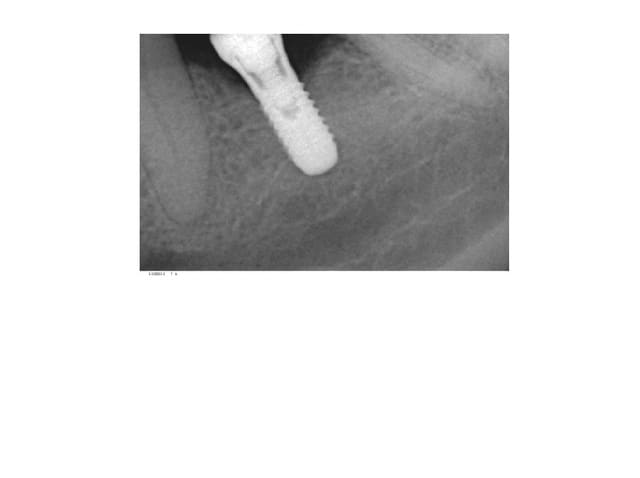

-un homme de 53 ans ,bonne hygiène ,2cigarettes par jour,36et46 extraites depuis 15 ans ,il y a 4 mois mise en place de 2 Aesthetica+.

pas de problèmes particuliers lors de la pose sauf que je prévoyait du D2 mais c'etait du D1 jai mis les 2 vis de cicatrisation,les suites operatoires etaientt normales avec une belle gencive attachée pas d'inflammation.surprise 4 mois plus tard cratérisation sur 36 et lyse angulaire. cliniquement pas de spires exposées,pas de mobilité,prévoir une accélération du phénomène apres mis en charge?merci de votre aide.

percussion claire au niveau de 46,36 ne génère pas de douleur,pas de mobilité ce type d'image sur un os dense traduit une réaction de la corticale (connectique a plat )plus qu'un échec d'osteointegration? dépose en prévention d'une mis en charge difficile?